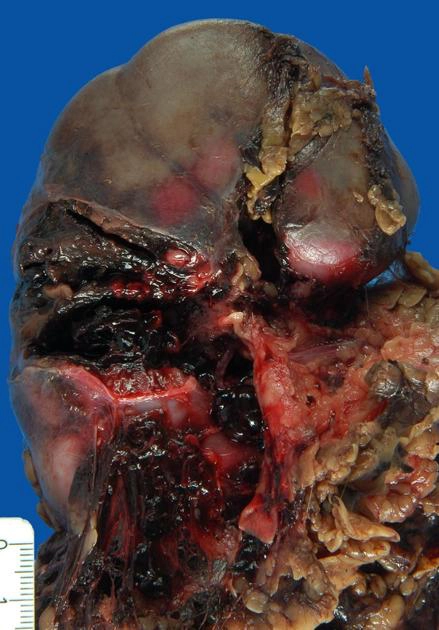

• Chấn thương thận

Chấn thương thận (Renal trauma)